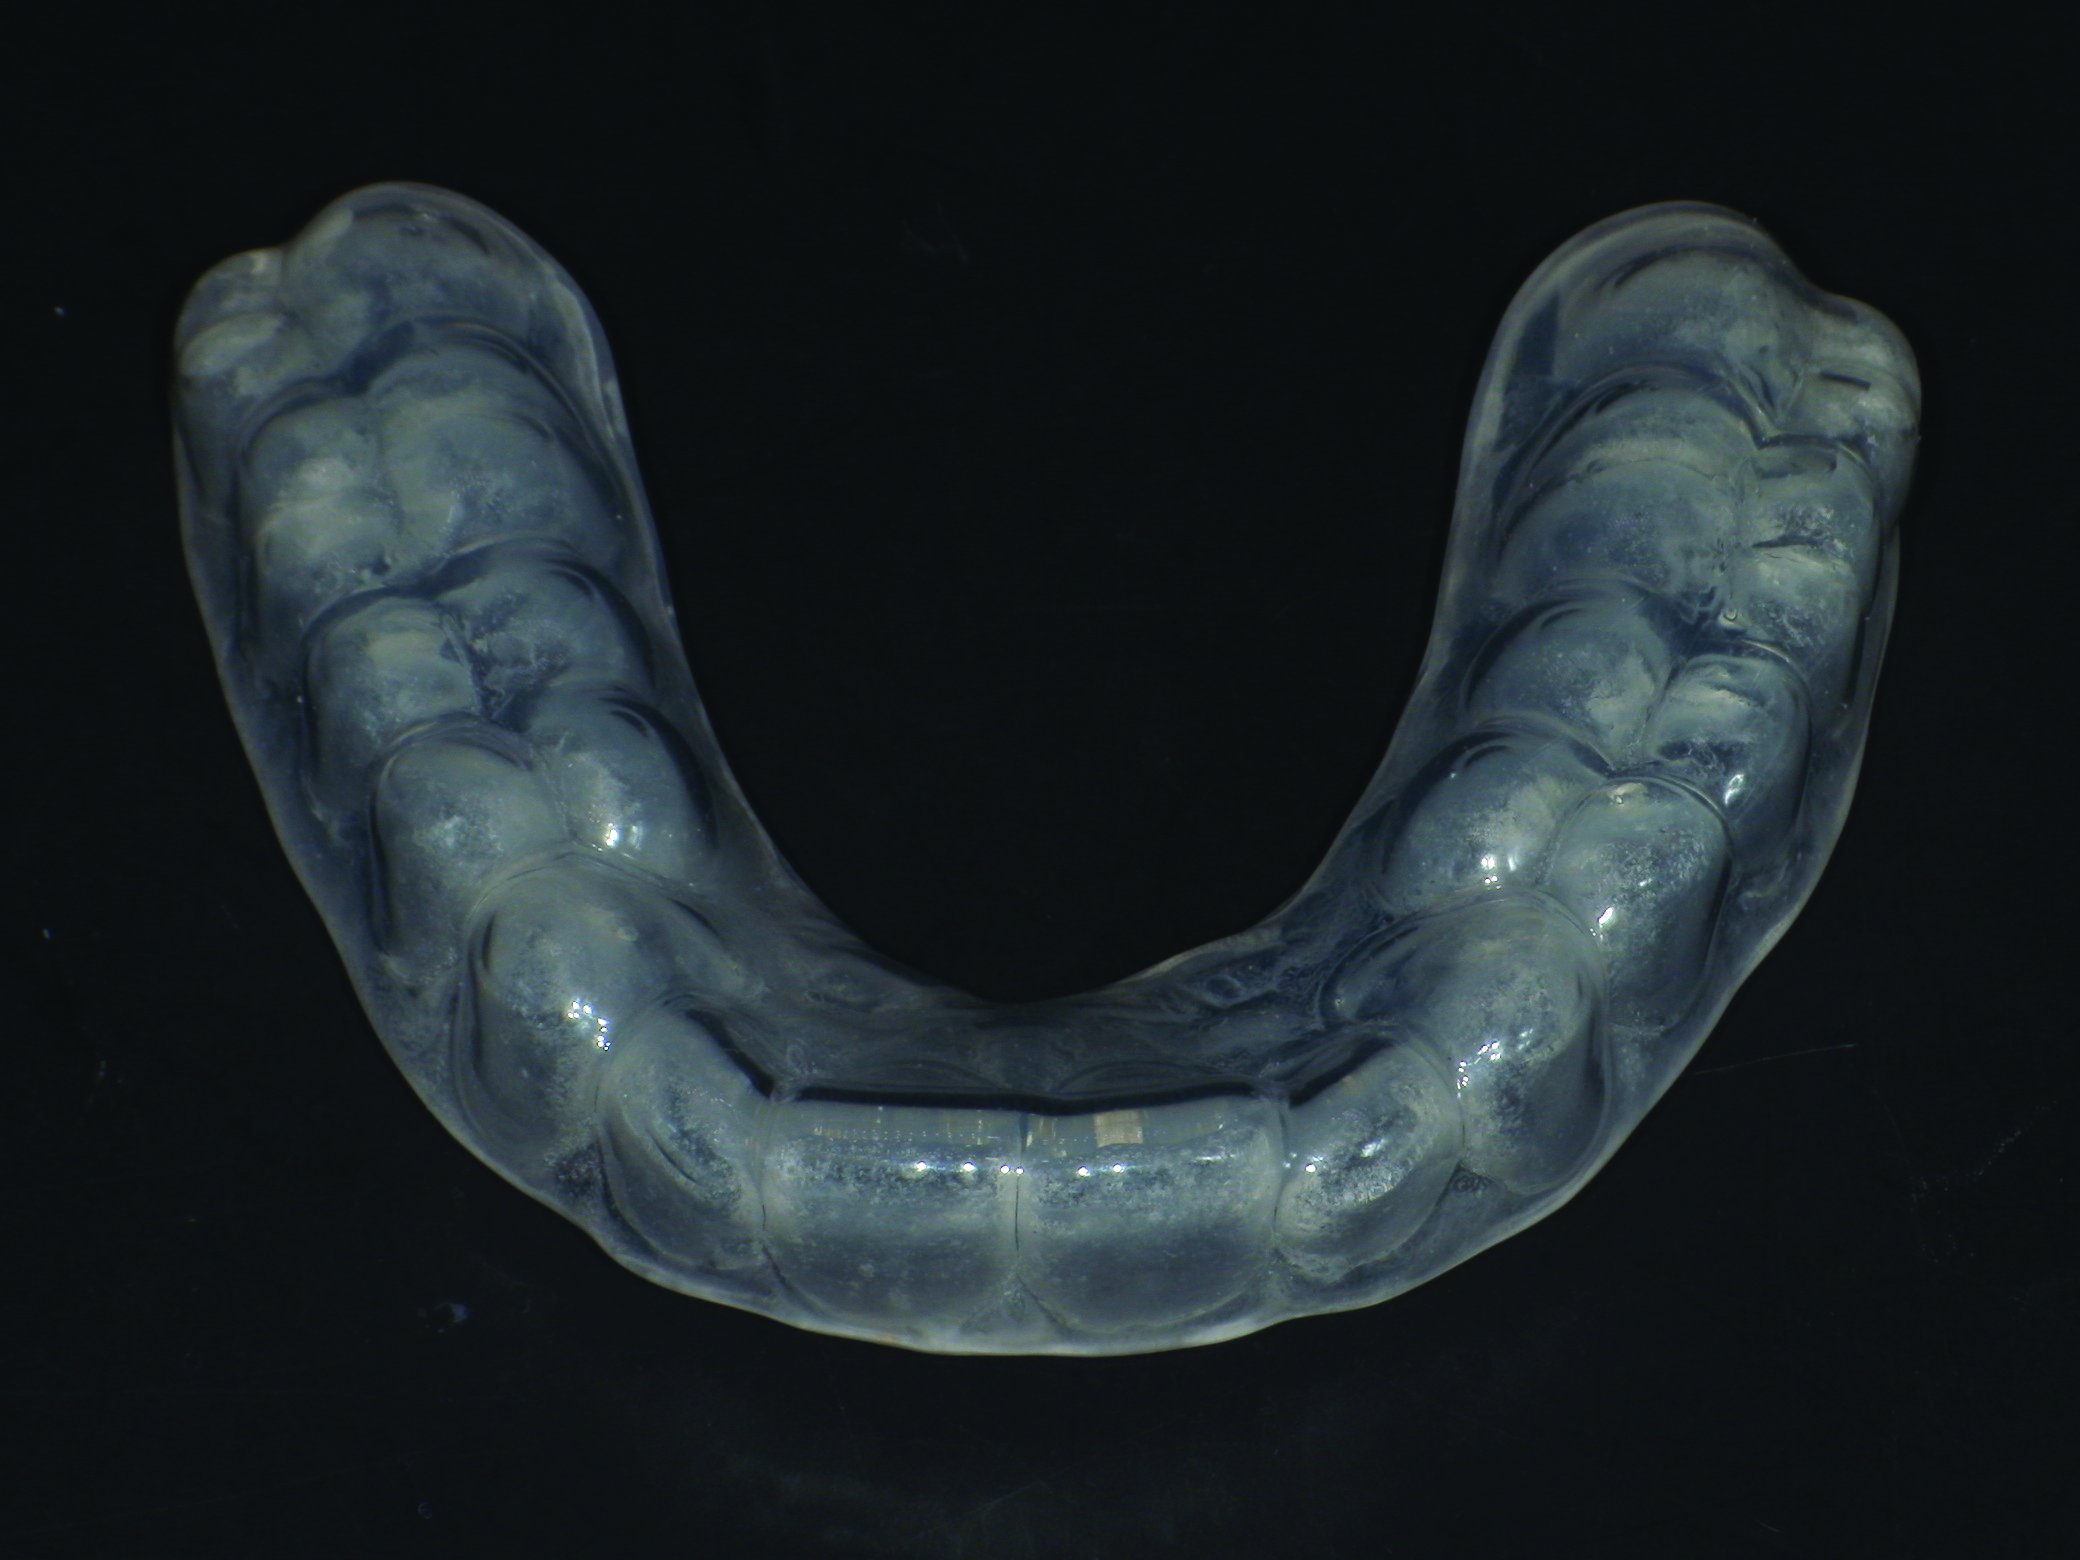

It should be noted that variation in the elastic modulus of the overlying laminate can significantly affect the device’s ability to prevent hard- and soft-tissue damage. Control over the thickness of in-office fabricated sports mouth guards can be obtained using combinations of inner and outer laminated layers.1 The finished product should have bilateral interocclusal contacts (Figure 7), cover all labial and lingual maxillary tooth surfaces, and have an open palate (Figure 8).

(8.) Retracted intraoral view and occlusal extraoral view, respectively, of the completed, dual-layer, custom-made sports mouth guard.